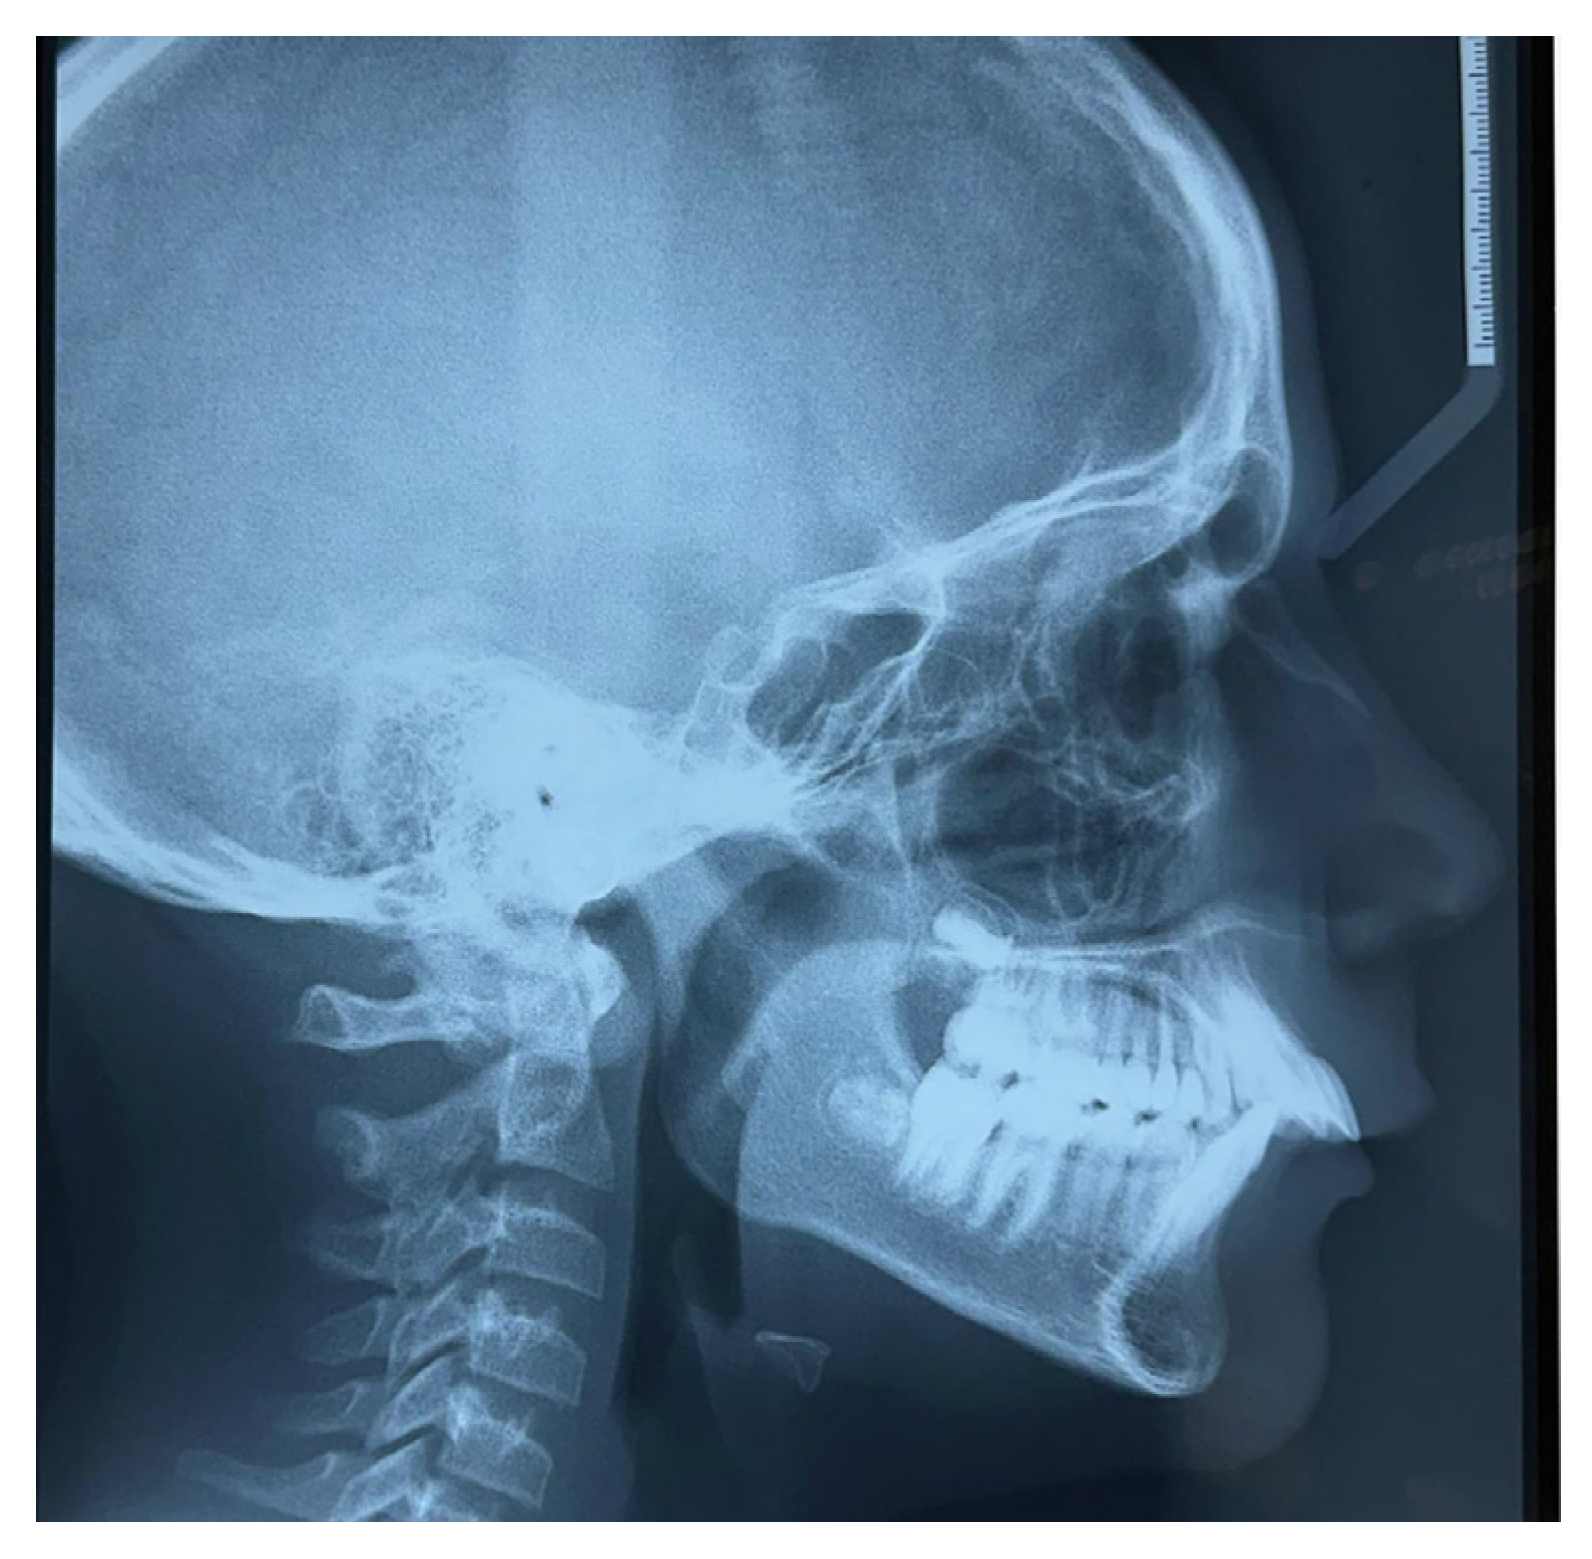

| Reference Values | T0 Measurements | T1 Measurements | |

|---|---|---|---|

| SNA angle | 82° | 82.5° | 82° |

| SNB angle | 80° | 75° | 79.5° |

| ANB angle | 2° | 5° | 2.5° |

| Wits appraisal | 0 mm | 4 mm | 2 mm |

| SN-GoMe angle | 32° | 35° | 36° |

| SN-SnaSnp angle | 8° | 7° | 6° |

| SnaSnp-GoMe angle | 26° | 28° | 30° |

| p.O.-GoMe angle | 16° | 19.5° | 17° |

| GoMe-GoPc angle | 126° | 128° | 122° |

| GoMe-GoN angle | 73° | 71° | 73° |

| GoN-GoPc angle | 53° | 57° | 49° |

| SGn-SN angle | 67° | 68° | 69° |

| SGo/NMe | 62% | 62% | 63% |

| I+/I− angle | 131° | 106° | 130° |

| SnaSnp-I+ angle | 109° | 126° | 105° |

| GoMe-I− angle | 90° | 102° | 102° |

| Overjet | 2 mm | 9 mm | 2.5 mm |

| NB-LsPgC angle | 8° | 17° | 11.5° |